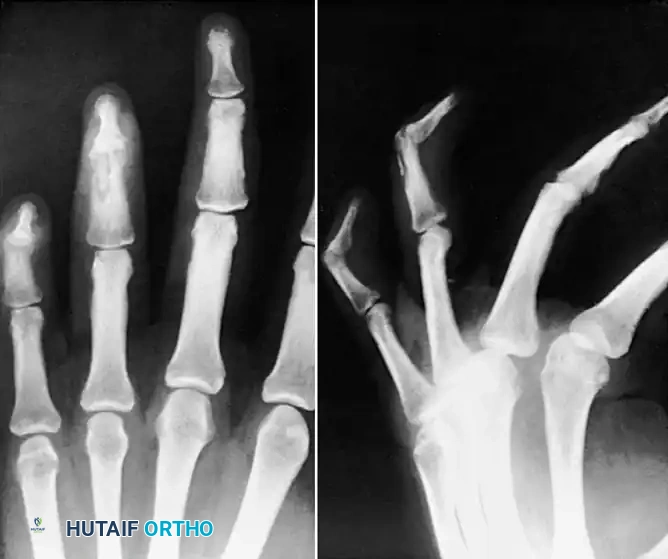

Radiographs in multiple planes are mandatory to rule out metacarpal fractures, osteochondral shearing injuries, and retained foreign bodies (tooth fragments).

* Fractures: Metacarpal neck fractures (boxer's fractures) are common.

* Osteochondral Defects: The tooth frequently gouges the metacarpal head. Chondral and osteochondral fractures occur in 6% to 59% of these patients, acting as a nidus for deep joint infection.